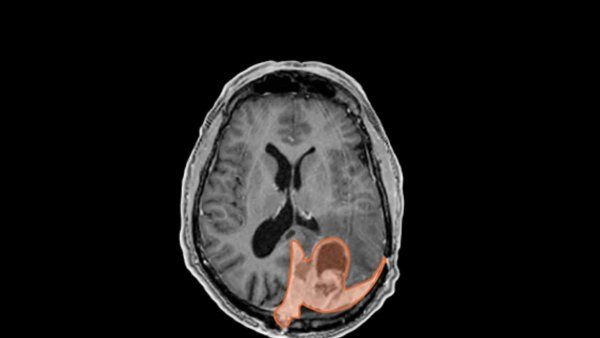

Researchers and clinicians at the UCSF Weill Institute for Neurosciences are working together to find better ways of monitoring, maintaining, and even enhancing brain health across the lifespan.

From autism to anxiety to Alzheimer’s, neurological and psychiatric disorders are among the most complex health challenges we face today. New technologies for observing and interacting with the brain and nervous system are changing how we understand and care for these diseases.